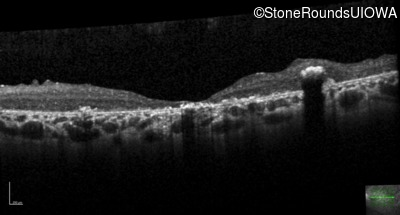

Optical Coherence Tomography - Left - 20/250 sc

Exemplar / OCT Stack